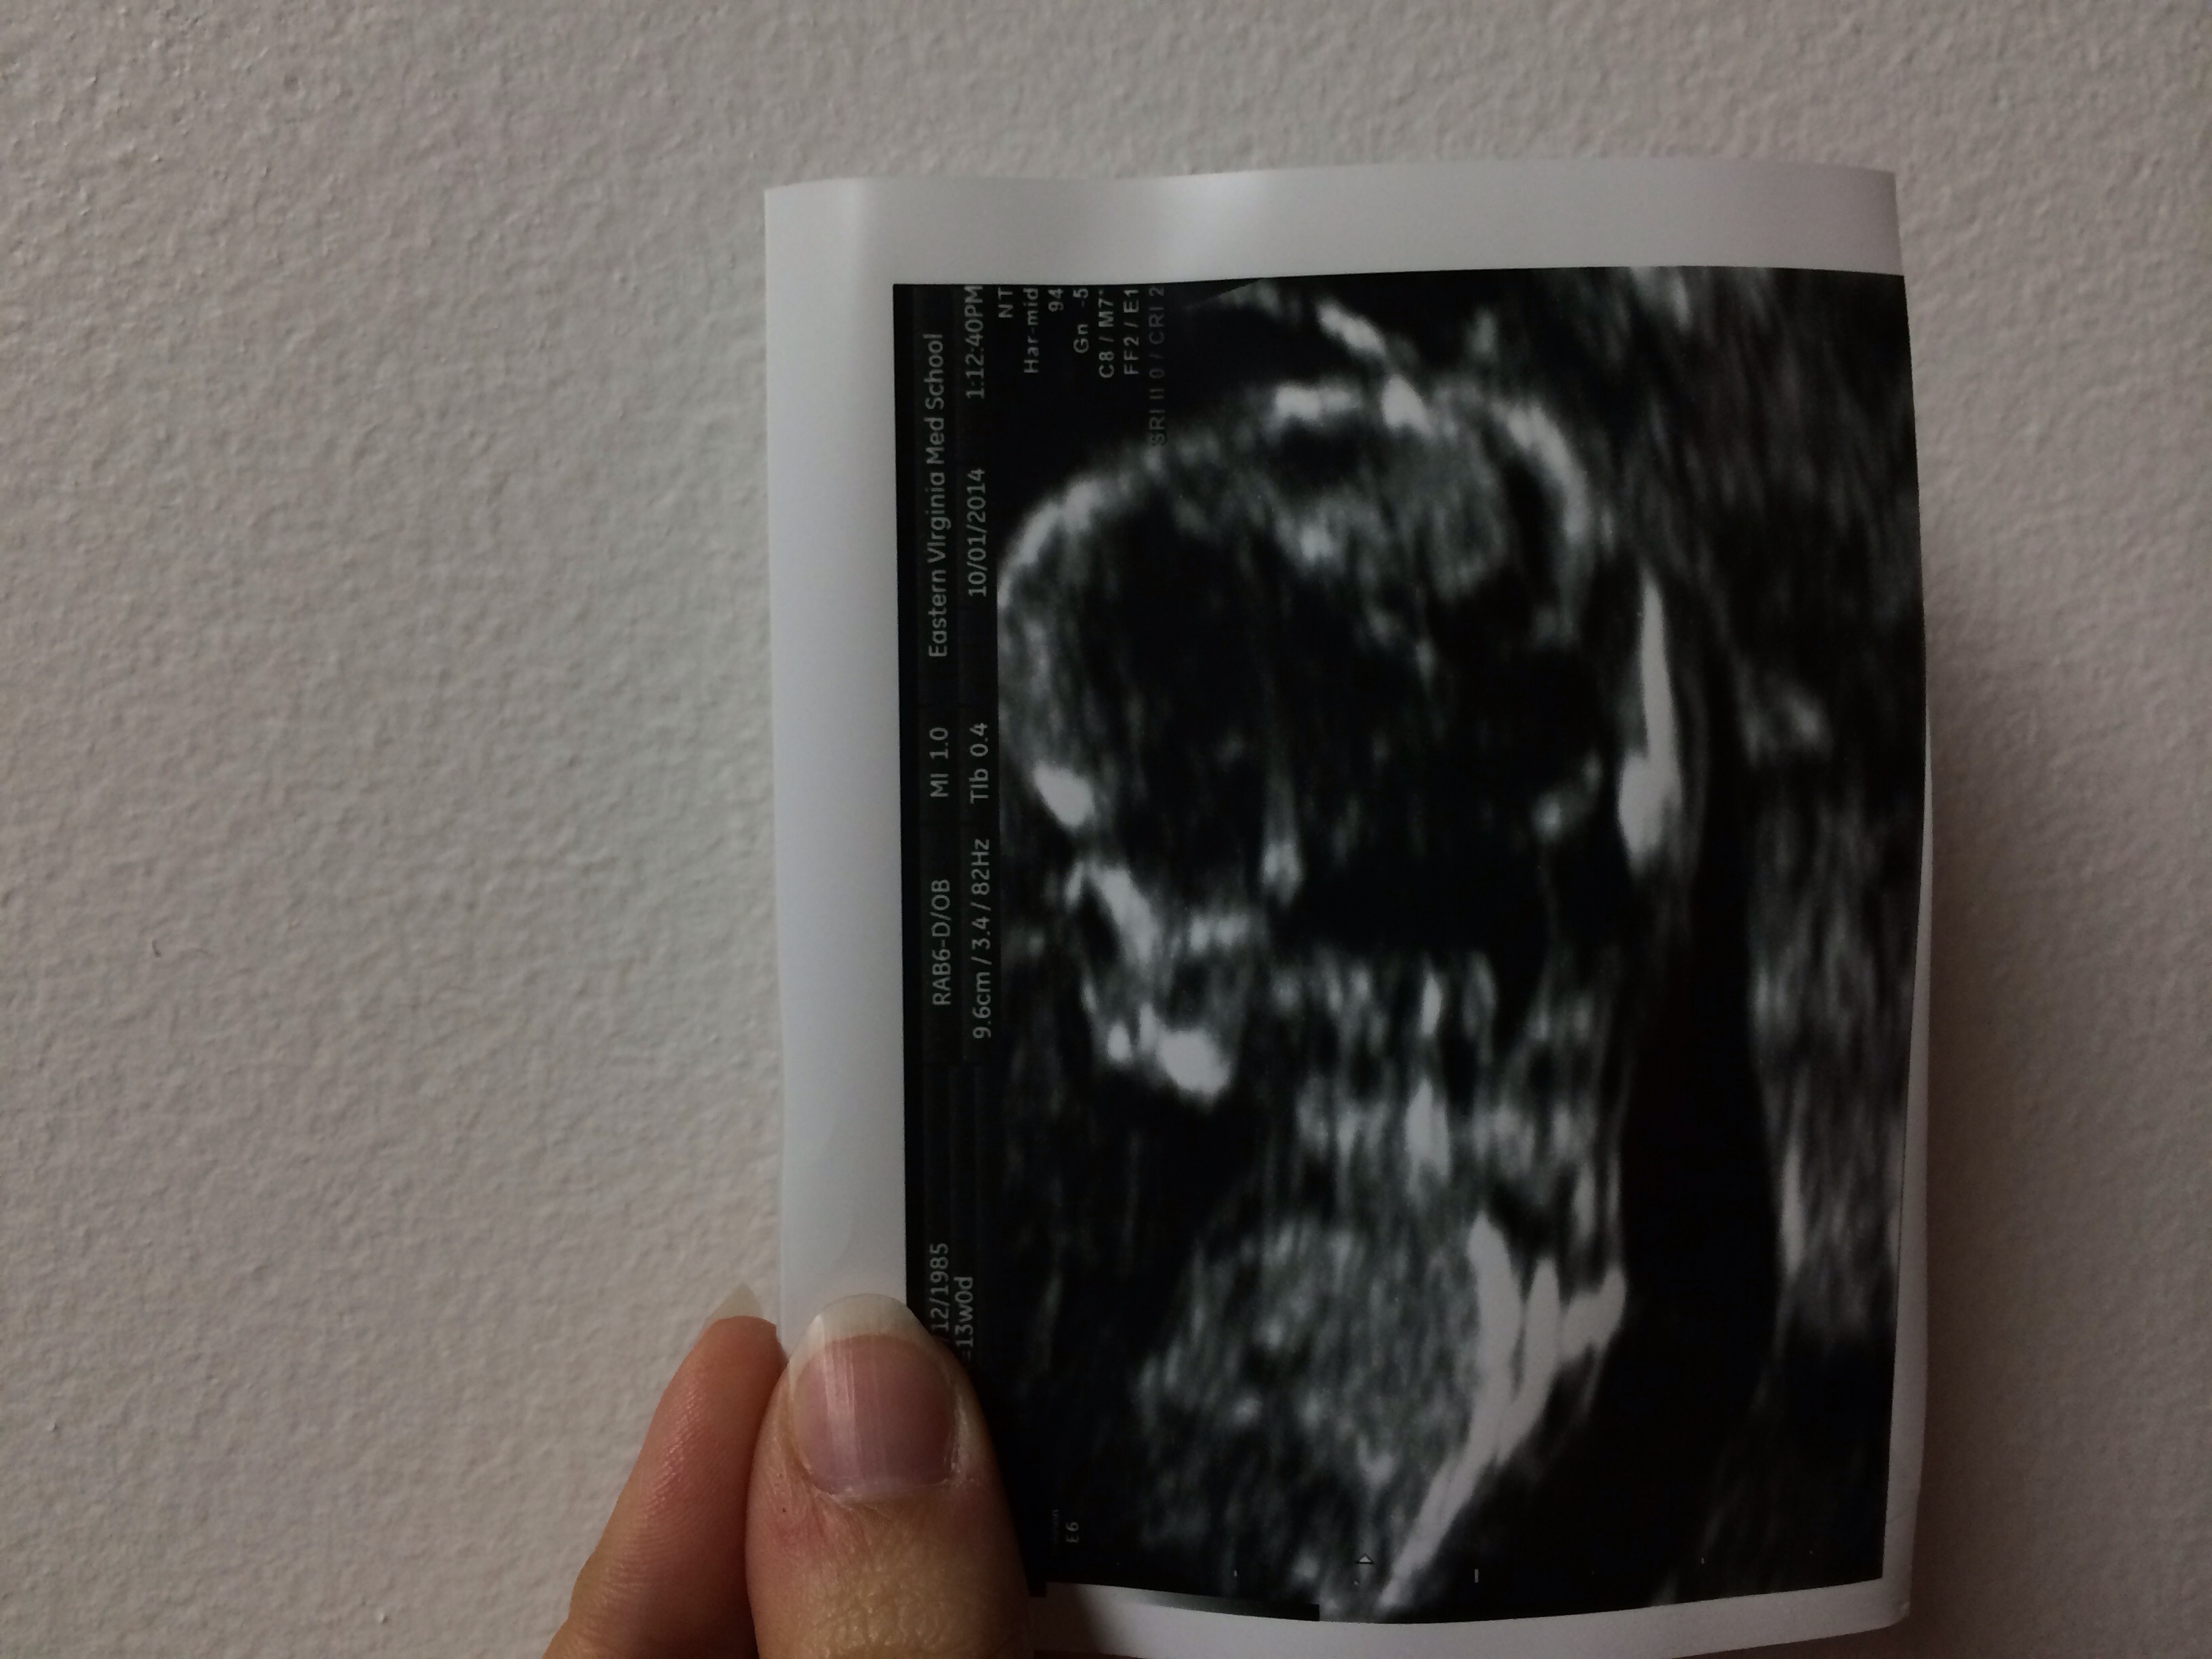

13 weeks today! Had our NT scan today and baby was squirming everywhere! Everything looks great and will let us know the blood results by next Wednesday! Ps, the nurse was TERRIBLE at drawing blood. Boo her!